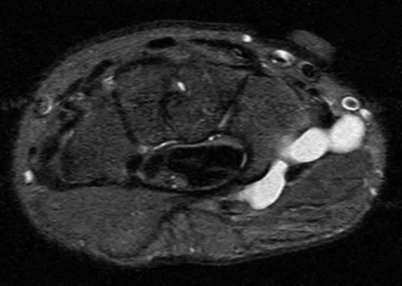

Contrast enhanced MRA of the wrist is typically used to diagnose hypothenar hammer syndrome or other vascular abnormalities.